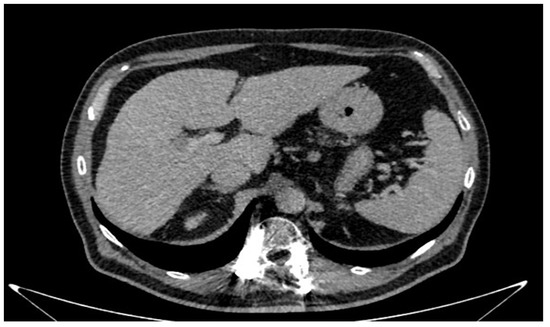

3.1. Case Presentation